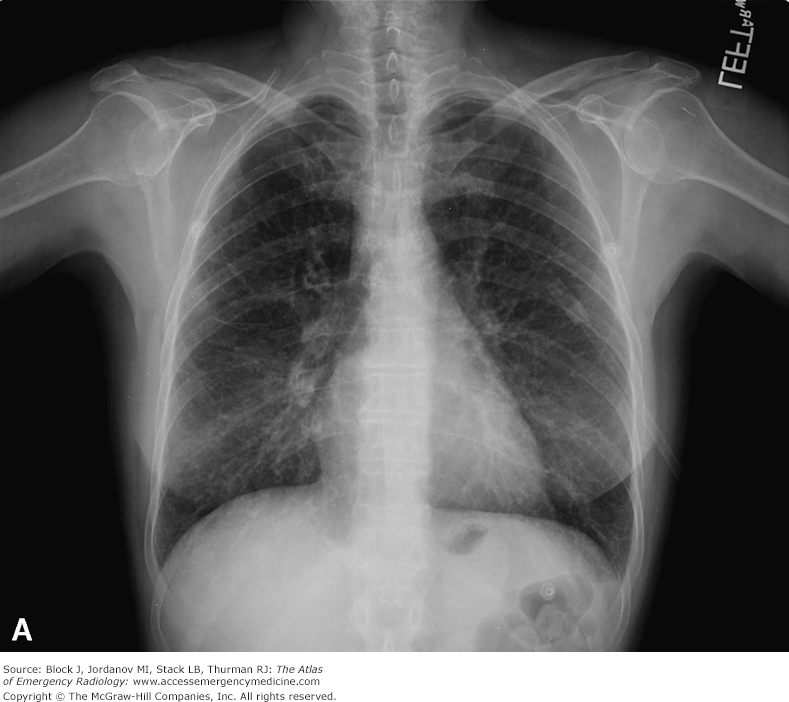

Frontal and lateral views of the chest demonstrate airspace disease on the lateral film (B) in the right lower lobe (white arrow) that may not be immediately apparent on the frontal film (you can see the pneumonia in the right lower lobe in [A] [black arrow]).

In this case, a right lower lobe pneumonia superimposed on the lower spine on the lateral view makes the spine appear “whiter” (more dense) just above the diaphragm. This is called the spine sign.